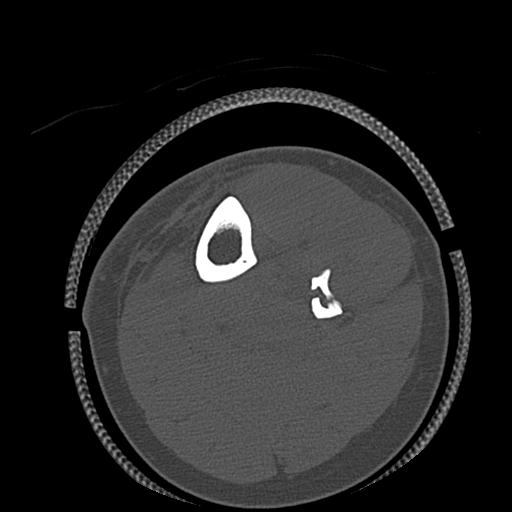

102803 1/12(キウスなし) 1/27 左下腿 4R 30歳女性 左脛骨軸内釘